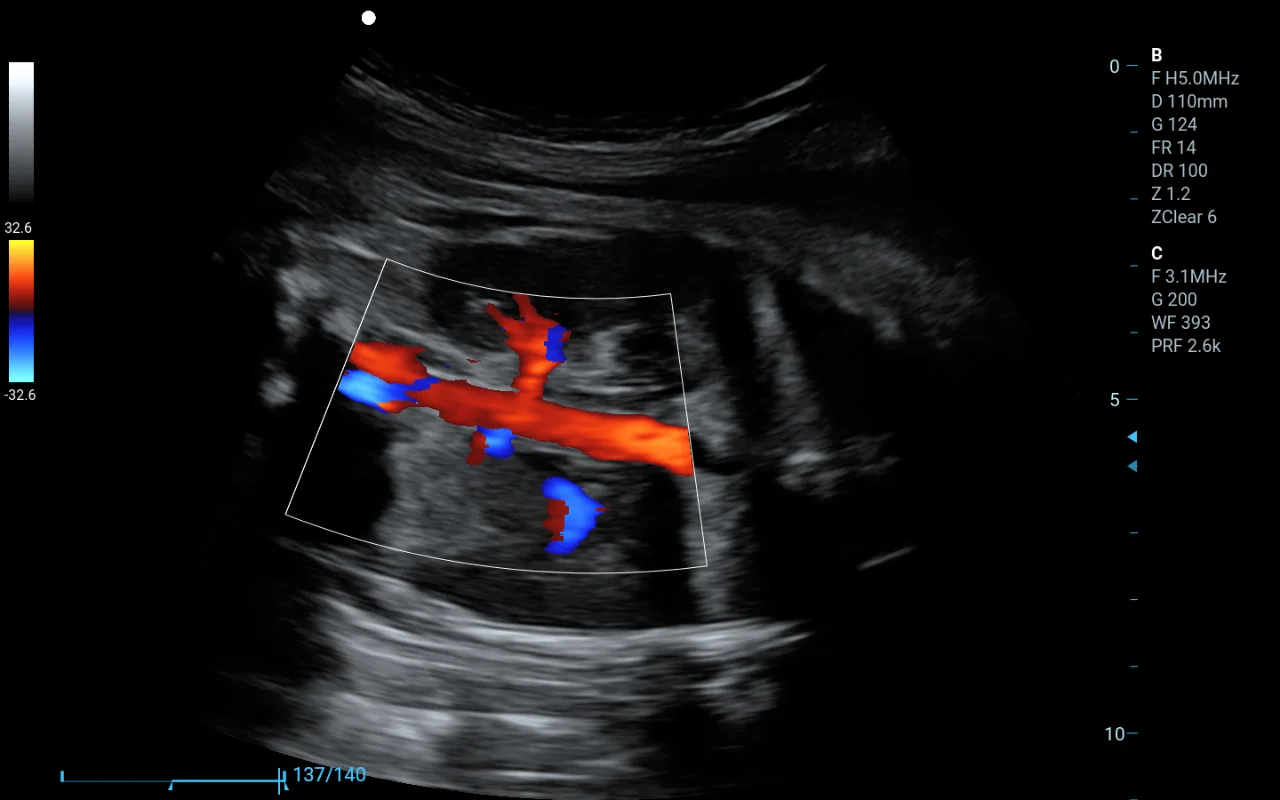

在醫(yī)院醫(yī)生可以利用這類軟件查看病人的CT或MRI影像,通過三維重建的圖像更直觀地判斷病變部位,這相當(dāng)于給醫(yī)生提供了一雙“立體眼睛”,但最終的診斷還是由醫(yī)生來完成。這就是為什么它屬于第二類,而不是更嚴(yán)格的第三類醫(yī)療器械。